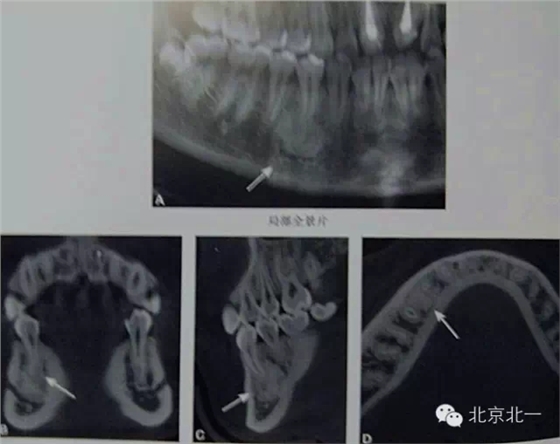

【CBCT表現(xiàn)】:

在CBCT上,根尖型骨島無(wú)低密度帶狀影包繞,與周圍骨質(zhì)分界清晰,具有特征性的毛刷樣邊緣,且其發(fā)生區(qū)域的牙根牙周膜影像連續(xù)、完整、不導(dǎo)致頜骨的膨隆。

右下頜C4根尖區(qū)課件一類圓形高密度影,與周圍骨質(zhì)分界清晰,C4牙周膜影像連續(xù)、完整,下頜骨未見(jiàn)膨隆。